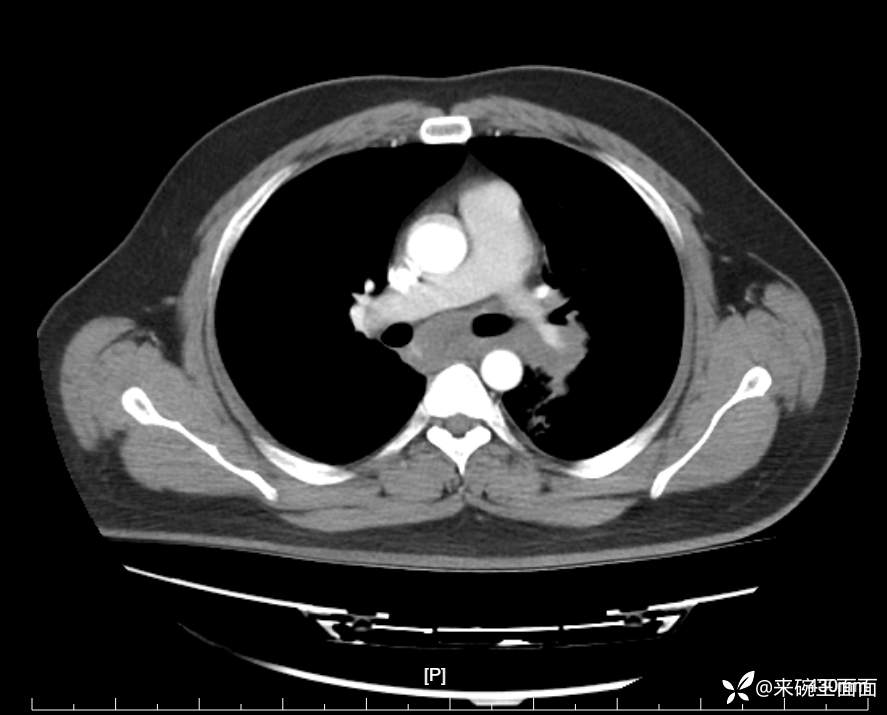

性别:男

年龄:27岁

主诉:胸闷胸痛数月余,休息后可自行缓解,无咯血症状。

个人史:数年吸烟史,具体不详。